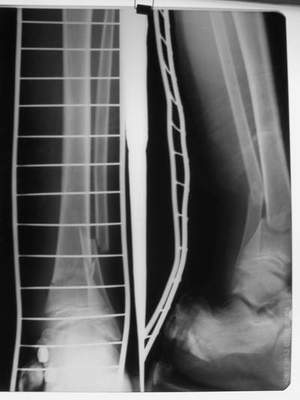

Операции: 1 Клиновидная резекция на вершине деформации м\берцовой кости.

2 Тугоподвижный ложный сустав н\3 б\берцовой кости. Рубцы выполняющие пространство между отломками, канал проксимального отломка иссечены.

Одномоментное устранение деформации, остеосинтез Г-образной пластиной.

Пластика по Хахутову.

Заживление проксимальной части раны вторичным натяжением без нагноения. Рана зажила. Спицы удалены через 1,5 недели после операции.

Учитывая фон (интеллект, etc) гипсовая повязка.

На данный момент ходит при помощи костыля (без присмотра -без костыля :), разрабатывает движения в г\стопном суставе.

В пределах 2 см.

Не катастрофа. Рост продолжается, будем следить в динамике.

Фиксация

Промежуточный